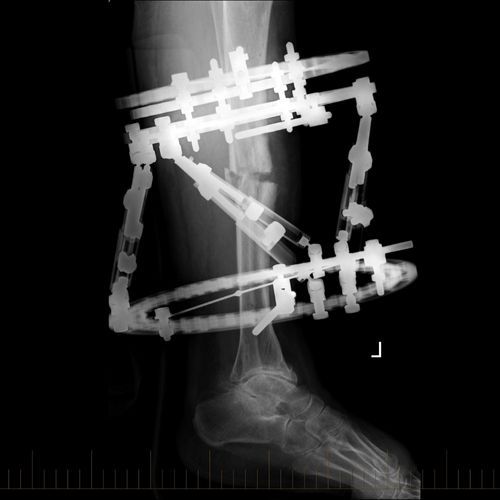

Adult with Circular Frame Correction of the Post-Traumatic Deformity of the Tibia